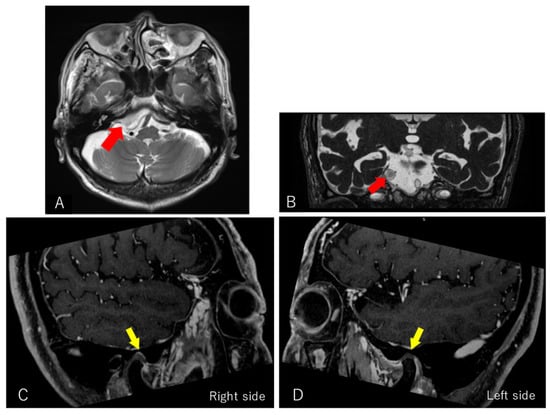

Our consultation with the neurologist revealed that the patient had a known medical history of hypertrophic pachymeningitis and TS. In March 2013, paresthesia and dysgeusia in the right trigeminal nerve innervation area were detected. In addition, the patient experienced difficulty in eating. In April 2013, he visited the Department of Neurosciences at [XX] and was hospitalized for dietary management and intensive examination and treatment. Head magnetic resonance imaging (MRI) was performed, and hypertrophic pachymeningitis and TS were suspected. No osteoarthritic change of the condyle and no articular disc displacement on both sides of the TMJ was found on multiplanar reconstructed MR images (Figure 5).

Figure 5. Axial (A) and coronal (B) T2-weighted magnetic resonance imaging showing a heterogeneously enhanced mass (red arrow). Reconstructed MR images showing no abnormal structure of the TMJ components. (C,D) The articular disc (yellow arrow) is in a correct position.